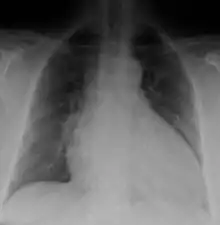

Generalized enlargement of the heart is seen upon normal chest X-ray. Pleural effusion may also be noticed, which is due to pulmonary venous hypertension.[28]

The electrocardiogram often shows sinus tachycardia or atrial fibrillation, ventricular arrhythmias, left atrial enlargement, and sometimes intraventricular conduction defects and low voltage. When left bundle-branch block (LBBB) is accompanied by right axis deviation (RAD), the rare combination is considered to be highly suggestive of dilated or congestive cardiomyopathy.[29][30] Echocardiogram shows left ventricular dilatation with normal or thinned walls and reduced ejection fraction. Cardiac catheterization and coronary angiography are often performed to exclude ischemic heart disease.[28]